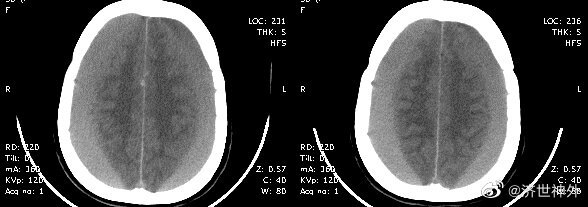

患者的艱難經(jīng)歷幫助醫(yī)生成長(zhǎng)——1例頑固性慢硬血腫在藥物治療下終于緩解

董世英的科普號(hào)2024年08月07日152